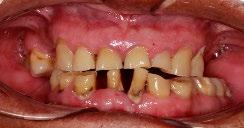

Figura 1. Fotografías clínicas intraorales oclusales, perfil derecho, frontales iniciales y radiografía panorámica en las que se observa caries, extrusión de piezas y ensanchamiento del ligamento periodontal.

Se reporta el caso de un paciente masculino de 74 años, con antecedentes de extracciones por caries, que acude a consulta por incomodidad al comer. Fue remitido al Centro Educativo Multidisciplinario de Rehabilitación Oral, Tarímbaro, Michoacán, en octubre de 2022. Al examen clínico se encontró cálculo dental generalizado, gingivitis localizada, movilidad dental, atrición en el sector anterosuperior e inferior, ausencia de piezas posteroinferiores y superiores, y alteración de la DVO. El análisis de fotografías clínicas intraorales mostró extrusión de raíces de piezas antagonistas en las zonas edéntulas,

oclusión borde a borde y retracción gingival (Figura 1). En los estudios imagenológicos se observó ensanchamiento del ligamento periodontal y caries (Figura 2).